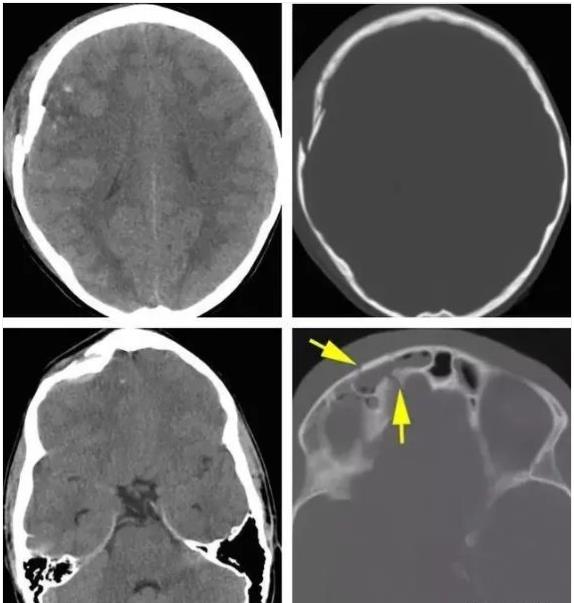

根据形态的不同,可出现凹陷、线状、粉碎性和空洞性等,外伤后颅内气体可提示颅骨骨折。